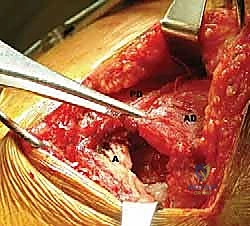

Identifying the Latissimus Dorsi and Teres Major:

- We'll identify the posterior border of the deltoid and retract it superiorly. Deep to this, we will find the latissimus dorsi and teres major muscles. The latissimus dorsi is typically more superficial and inferior to the teres major at this level.

- Surgeon's Directive: "Now, identify the interval between the deltoid and the underlying structures. We're looking for the characteristic fibers of the latissimus and teres major. Feel the muscle bellies – the latissimus is broad and flat."

Dissection of the Latissimus Dorsi Tendon and Humeral Insertion:

- Carefully dissect along the superior border of the latissimus dorsi, separating it from the teres major tendon. This is where we need to be acutely aware of the neurovascular structures.

- Surgeon's Directive: "Let's use our blunt dissection here initially, then sharp dissection as needed. We're working towards the humeral insertion. Remember the 180-degree twist of the latissimus fibers."

- Crucial Step: Identify the conjoined tendon if present (30% of cases). If so, carefully separate the latissimus from the teres major using sharp dissection.

- Surgeon's Directive: "Maintain constant awareness of the radial nerve. It lies anterior to the latissimus. We'll internally rotate and adduct the arm to increase its distance from our working field, but we must protect it throughout this release."

FIG 4 • B. The latissimus dorsi (L) is identified and separated from the teres major (TMa).